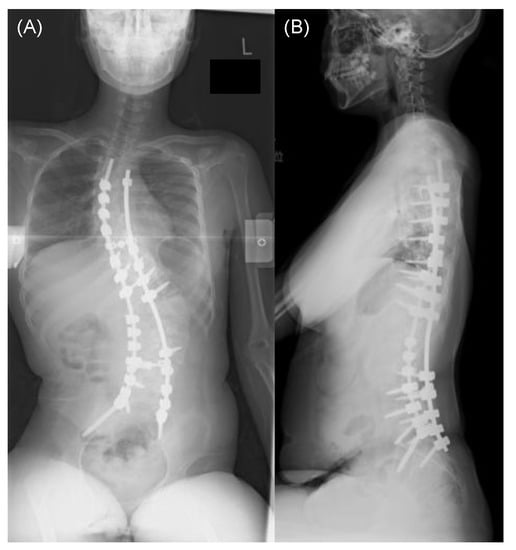

Representative Case Presentation